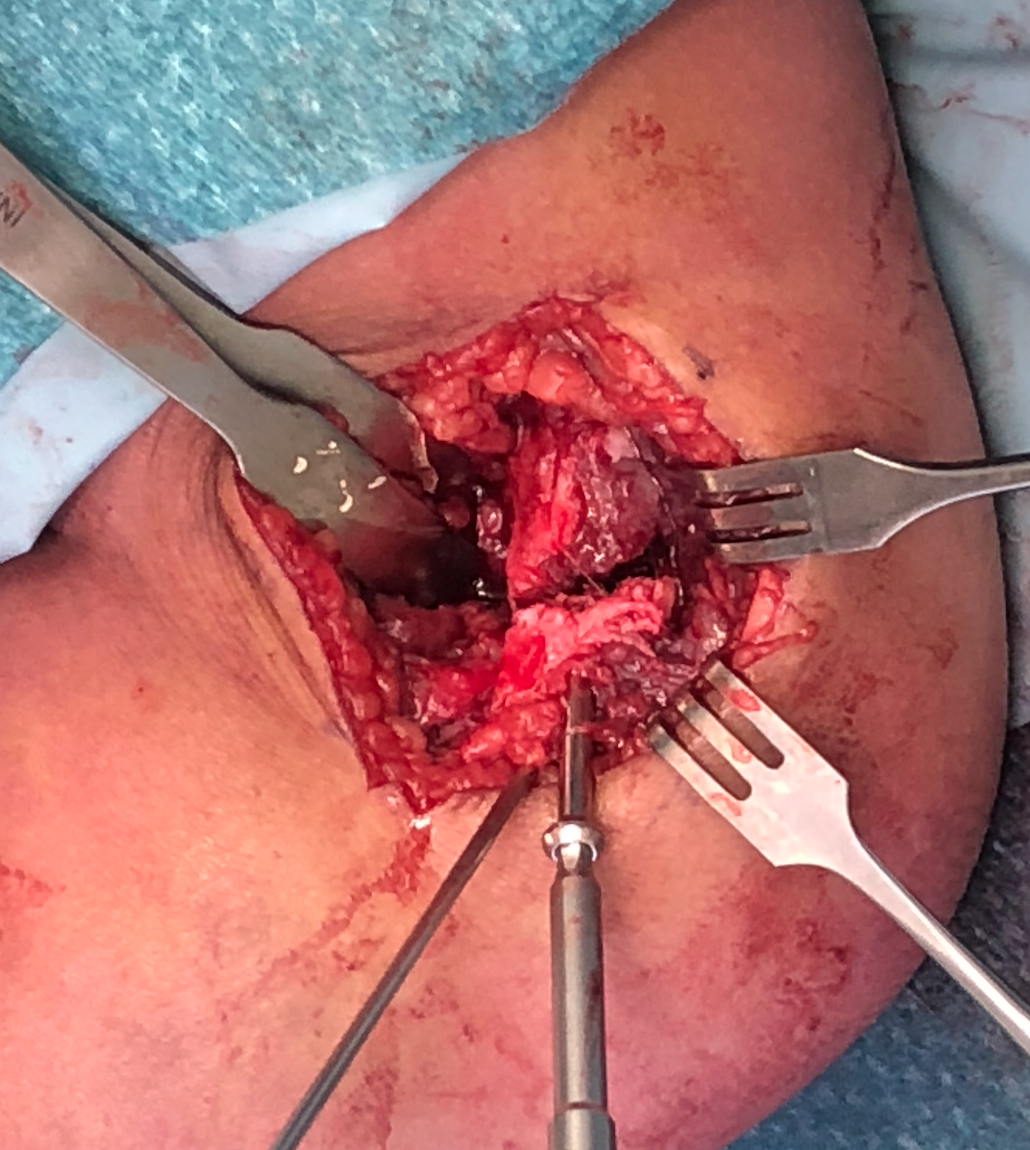

Lateral approach to distal humerus

- curved incision over lateral supracondylar ridge of humerus, and over proximal radius

- proximally intermuscular interval between brachioradialis & triceps

- proximally elevate brachioradialis and ECRL off the distal humerus

- distally split common extensor origin between ECRB and EDC and elevate anteriorly

Don't dissect posteriorly to protect blood supply

Don't need to dissect distal fragment

Use anterior homan retractor across distal humerus to elevate anterior capsule

- visualize distal joint line and perform anatomical reduction under vision

- one K wire parallel to joint surface across fracture into trochlea

- one K wire at 45 degrees to first engaging medial metaphysis

- bury K wires as need to be in for 6 weeks

Open reduction of displaced lateral condyle in left elbow